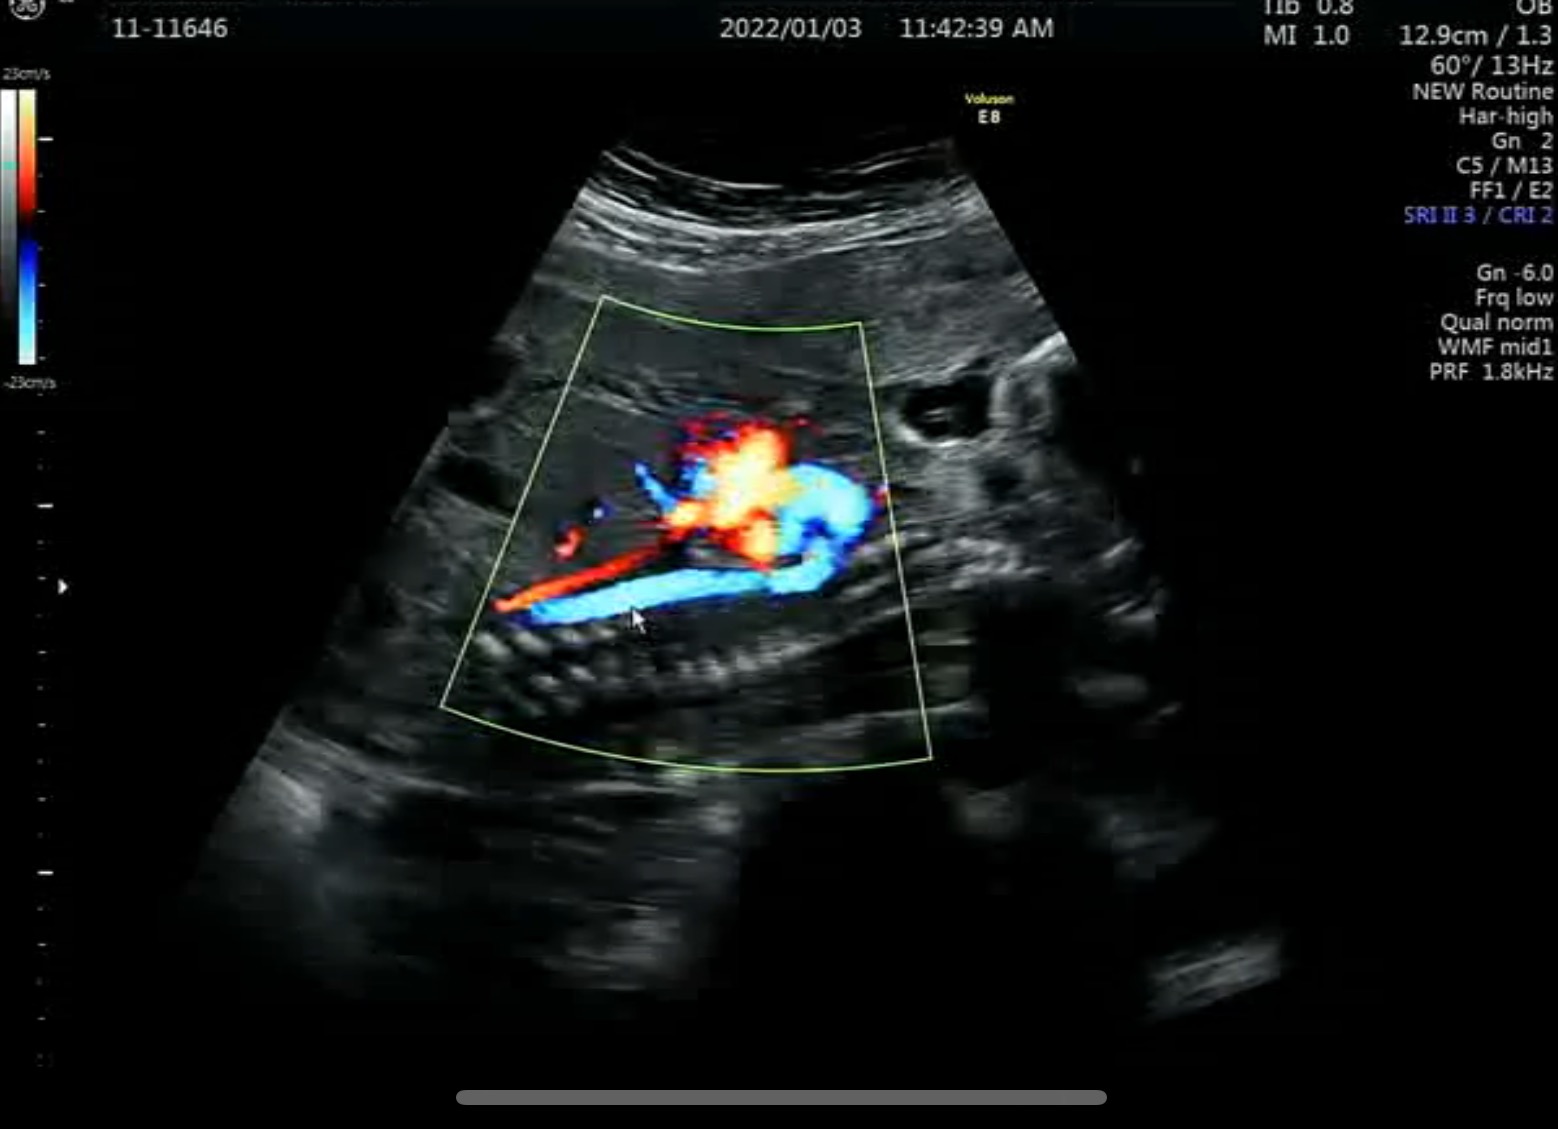

탯줄에 보이는 혈관도 3줄로 정상으로 보인다고..